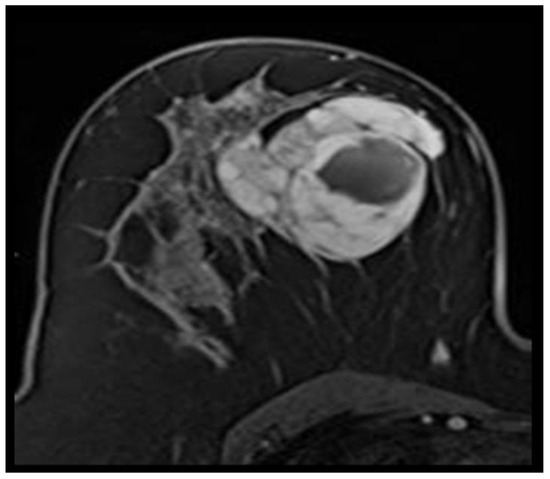

Non-Hodgkin’s malignant lymphomas are a heterogeneous group of hematological malignancies, characterized by a variety of clinical, morphological, histopathological, immuno-histochemical, molecular and evolutionary features. They represent a form of c...